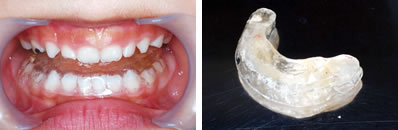

一見すると、あまり難しい反対咬合には見えませんが、実は下あごを無理に後ろに押し下げている状態で普段過ごしています。そのため、顎の関節に不具合が生じていました。

また、上顎には一部乳歯が残っているのですが、もう抜けそうになっていたので、その隙間をどうするかも問題となっていました。それに加え、上顎の2番目の永久歯(側切歯)が通常より幅が狭い「矮小歯」だったので、隙間が開いているなどの問題も重なっていました。

さまざまな問題をふくんでいたので、最新のCAD技術を応用した矯正治療分析ソフトを用いて治療計画を立てて、動画で治療経過予測を説明しています。

普段のかみ合わせのまま下顎を後ろに押し下げようと力をかけた場合、上顎前歯と下顎前歯がぶつかって上顎まで後ろに下げようとする力が働いてしまいます。そこで、チンキャップを使用する場合には前歯の干渉を避けるためにクリアプレートを併用しました。